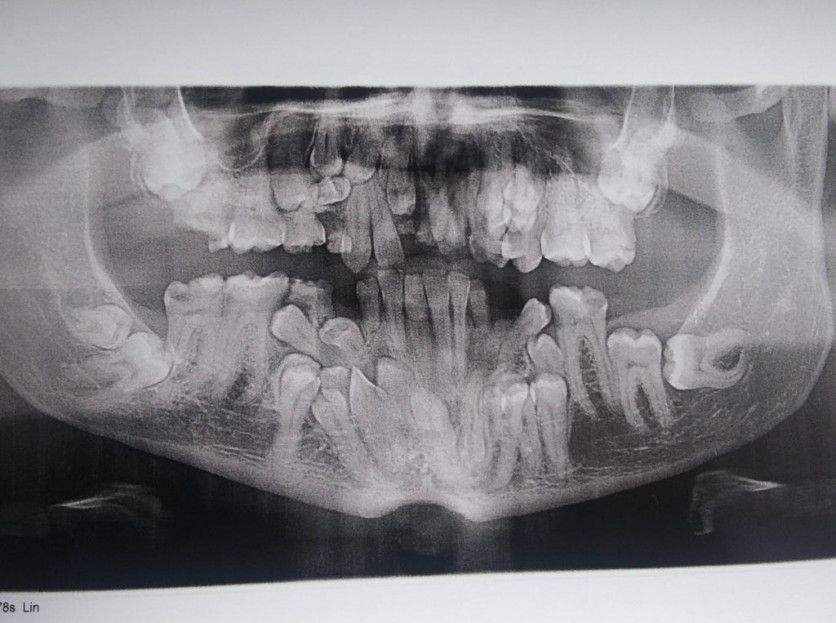

Desde su descubrimiento en 1895 por parte del profesor alemán Wilhelm Röntgen los rayos X han jugado un papel fundamental en las sociedades humanas. Son usados en campos tan distintos como el sanitario, la seguridad en el transporte e incluso la identificación de obras de arte. Su utilización está tan extendida que a veces deja imágenes tan curiosas como las recogidas en esta galería.